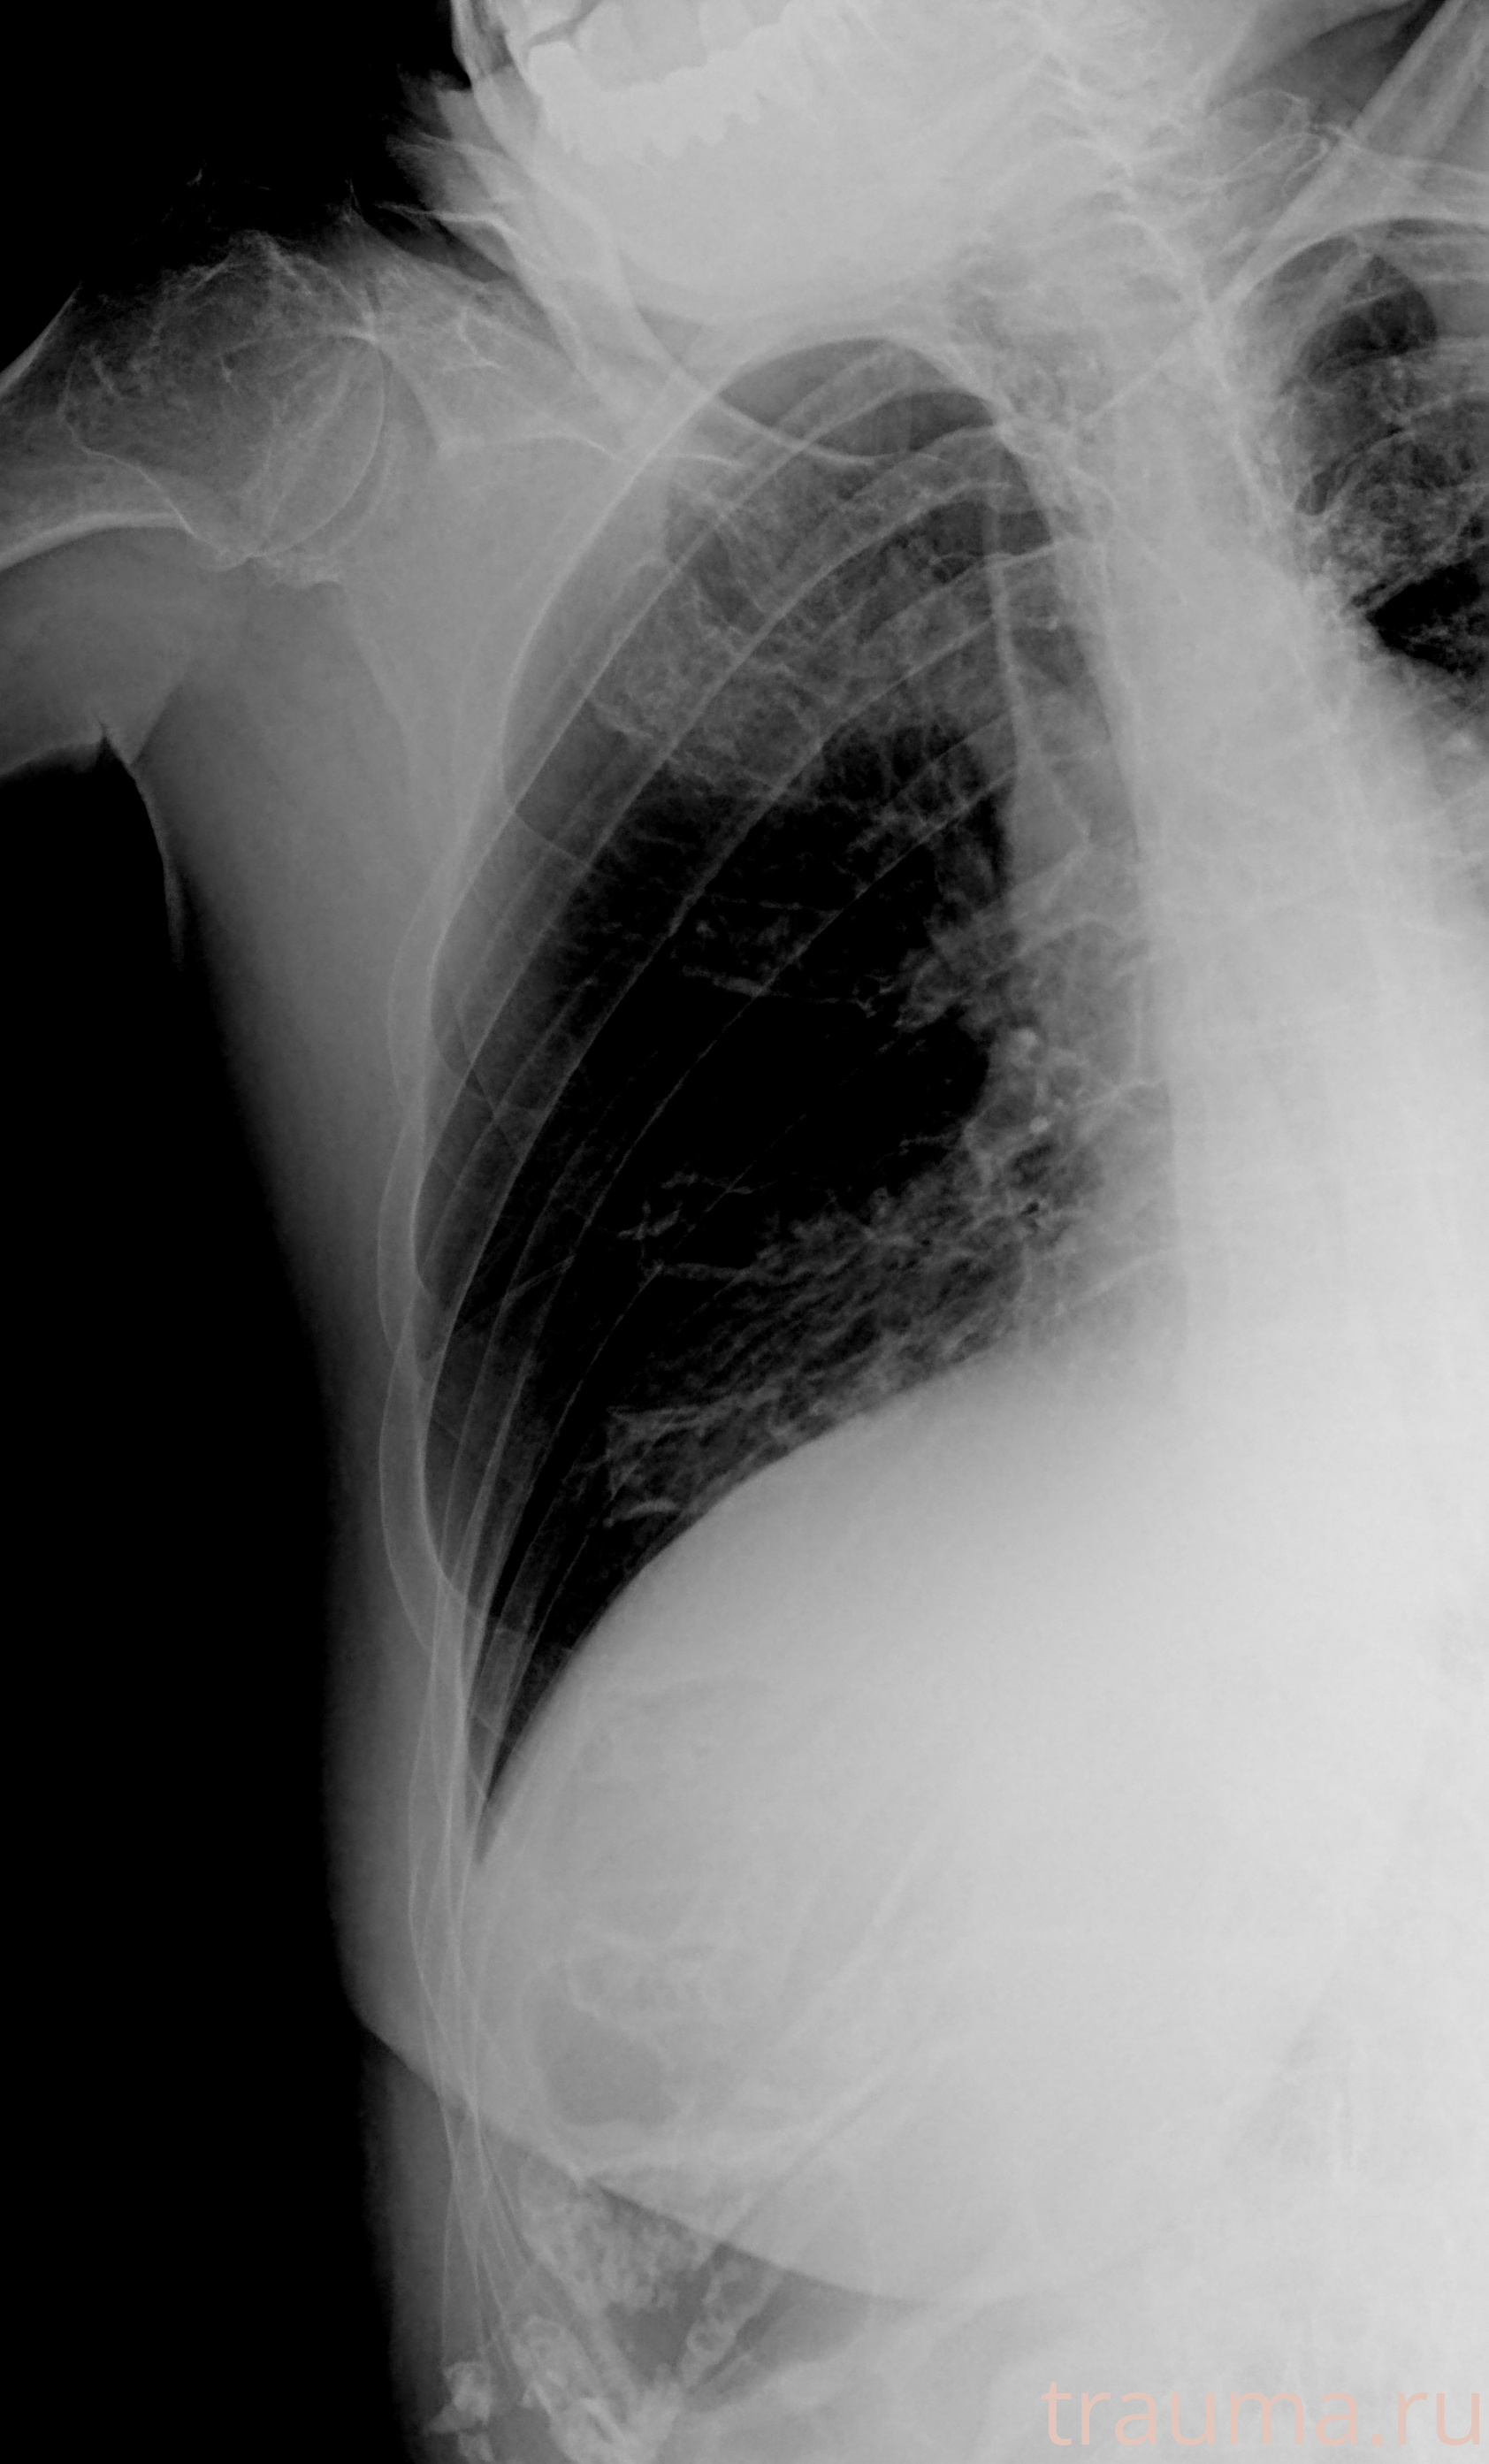

Рентгенограммы

Рентген на дому: по вашему адресу приезжает врач-рентгенолог, травматолог-ортопед с мобильным рентгеновским аппаратом, проводит диагностику травмы или заболевания, делает необходимые рентгенограммы, дает рекомендации по дальнейшему лечению. Получить качественные снимки в домашних условиях возможно благодаря уникальной методике, разработанной МосРентген Центром для института  Склифосовского